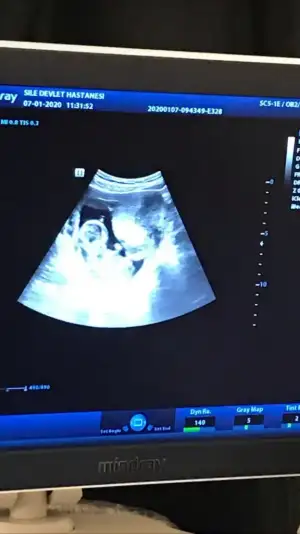

mrhaba lütfen yorumlarmisiniz sizce kızmı erkekmi bi arkadas icin soruyorum

Sevgili İkra,

Yorumlarsan çok sevinirim. ☺️❤️